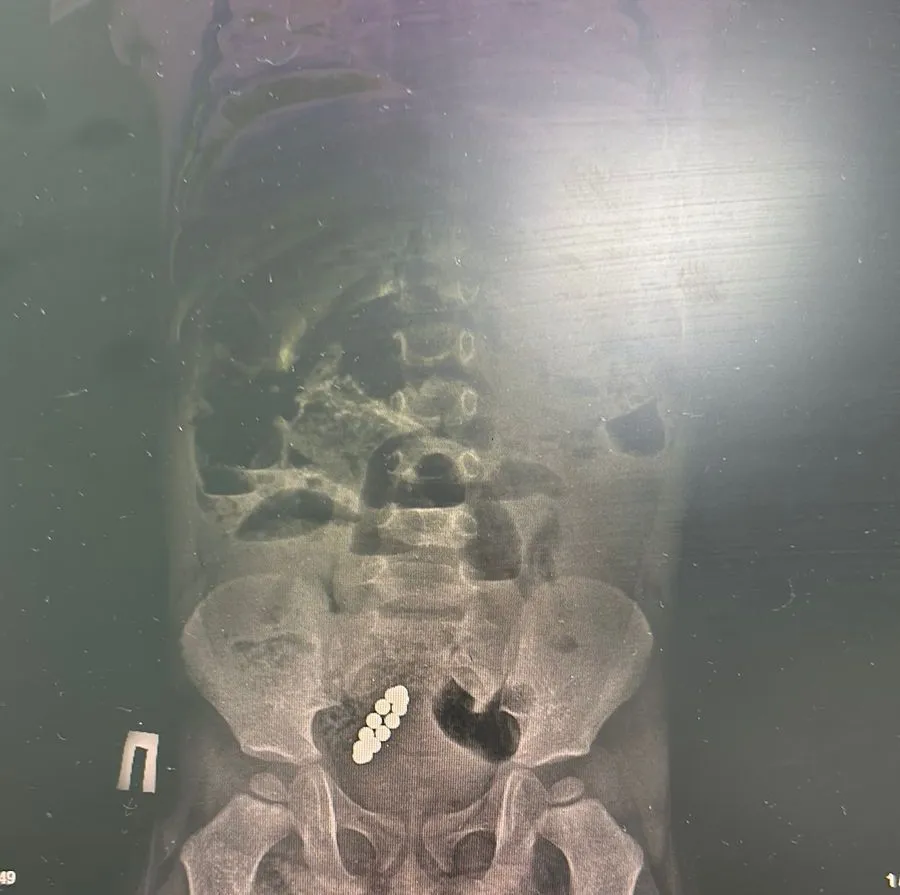

Врачи диагностировали острую кишечную непроходимость, перитонит и инфекционно-токсический шок. Оказалось, малыш проглотил магнитный конструктор, в кишечнике нашли 13 мелких деталей.

Сначала они заметили его недомогание и отвезли в частную клинику, рентген выявил инородное тело в кишечнике.

Диагноз был тот же – острая низкая кишечная непроходимость и инородное тело в желудочно-кишечном тракте.

«Нам пришлось выполнить две сложные операции: срединную лапаротомию, устранение кишечной непроходимости, удаление 13 магнитов, наложение тонко-тонкого анастомоза, санацию, трансанальную интубацию и дренирование брюшной полости. Врачам удалось спасти ребёнка».